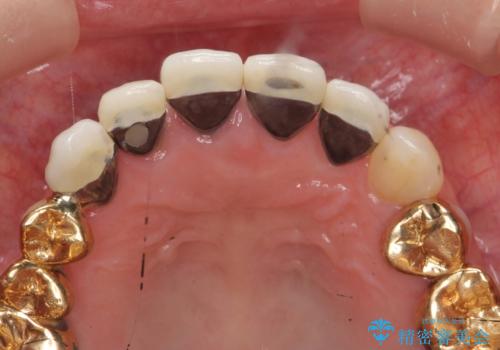

- 前歯の痛み・排膿・ぐらつきの改善を求めて来院されました。

視診・X線写真検査より根尖性歯周炎が認められ再治療が必要な状態です。

再根管治療を行うべくクラウン除去を行ったところ、右上側切歯に保存不可能な垂直性の破折が認められたため抜去が必要になりました。

即切歯の抜歯を行う場合犬歯を含めたブリッジによる補綴計画を立てることが多いですが、今回は犬歯から大臼歯にかかる大きなブリッジが既に装着されていたため予算とご希望を相談し前歯のみの延長ブリッジ補綴で治療を行っていくこととしました。